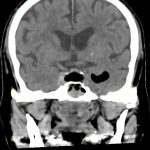

症例 '16年8月

No.

年_番号

手術年月

患者年齢

’16_117

'16年8月

70代

病名

術式

備考

下垂体腺腫

(円蓋部)

断層撮影

手術前

1

手術前2

手術後